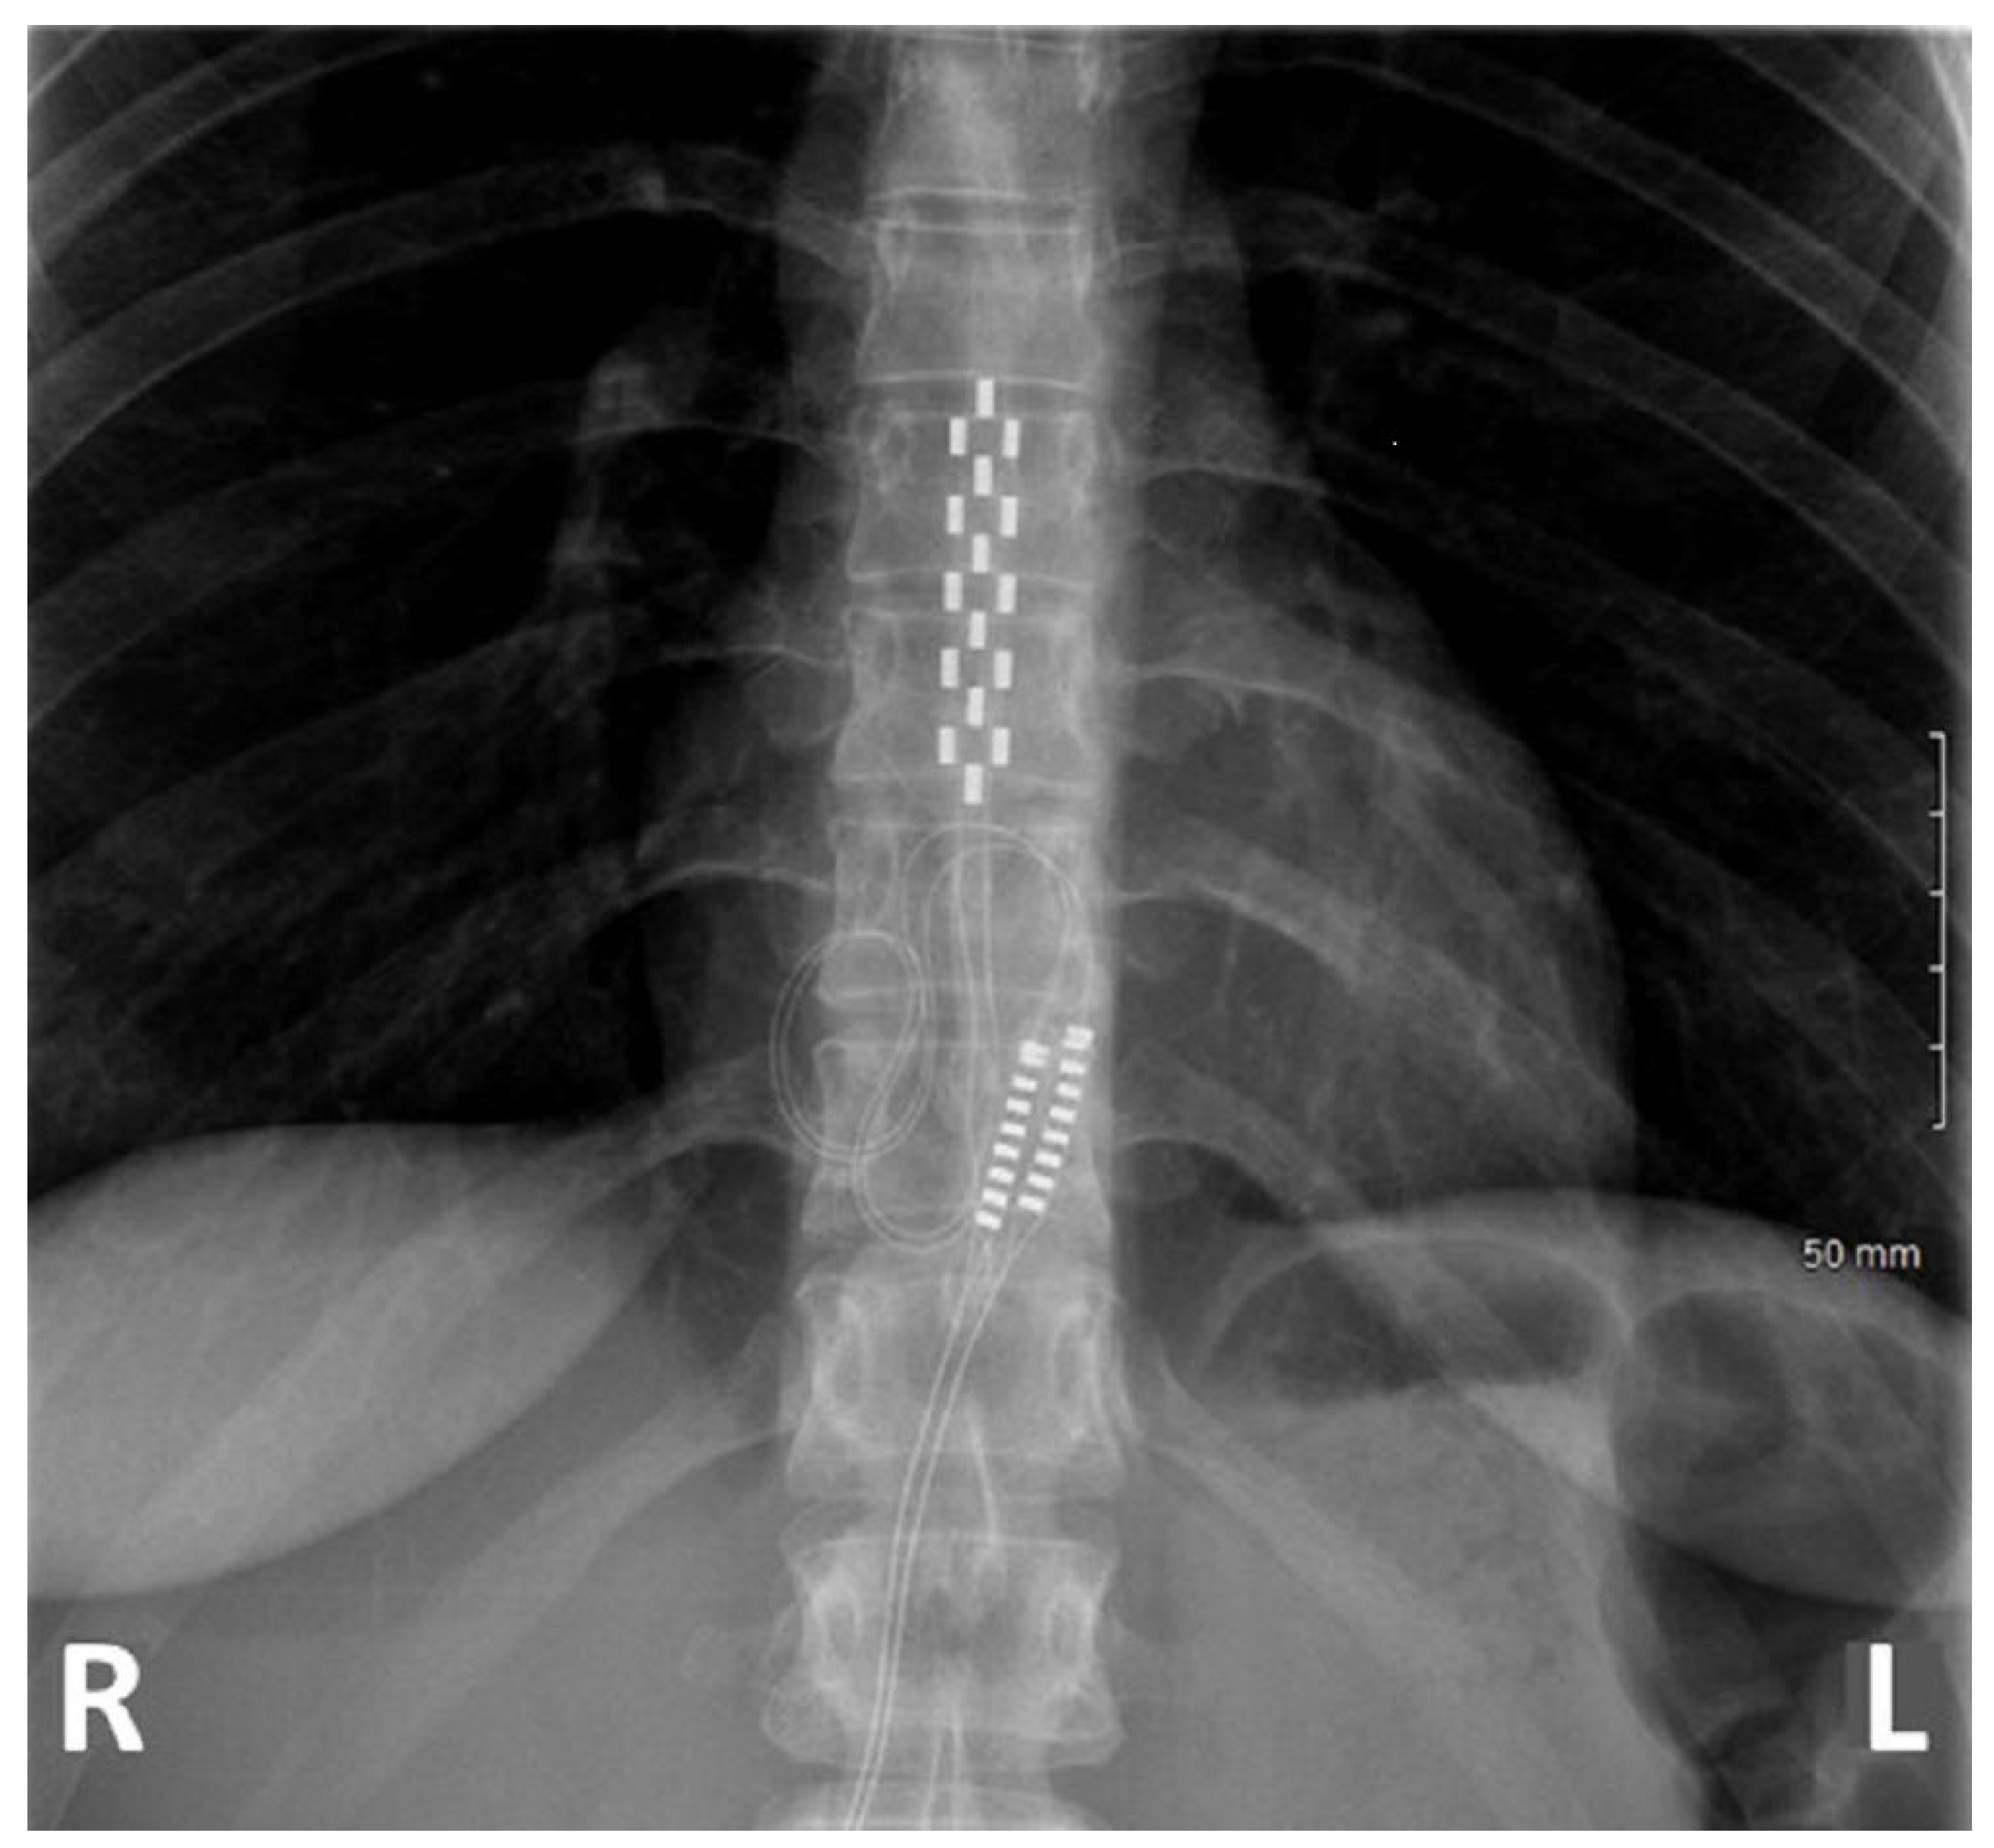

| MISAA Group n = 23 | MISGA Group n = 52 | LGA Group n = 33 | p-Value of the Difference | |

|---|---|---|---|---|

| Vertebral level projection of the conus medullaris | 0.12 | |||

| T11-T12 | 0 (0%) | 5 (9.6%) | 0 (0%) | |

| T12-L1 | 15 (65.2%) | 28 (53.8%) | 25 (75.8%) | |

| L1-L2 | 8 (34.8%) | 16 (30.8%) | 7 (21.2%) | |

| L2-L3 | 0 (0%) | 0 (0%) | 1 (3.0%) | |

| Unknown | 0 (0%) | 3 (5.8%) | 0 (0%) | |

| Lead lateralization (Upper/lower) (n, %) | 0.003 | |||

| Right/Right | 2 (8.7%) | 9 (17.3%) | 1 (3.0%) | |

| Right/Left | 0 (0%) | 0 (0%) | 1 (3.0%) | |

| Right/Midline | 7 (30.5%) | 3 (5.8%) | 6 (18.2%) | |

| Left/Right | 0 (0%) | 0 (0%) | 0 (0%) | |

| Left/Left | 0 (0%) | 5 (9.6%) | 1 (3.0%) | |

| Left/Midline | 5 (21.7%) | 3 (5.8%) | 1 (3.0%) | |

| Midline/Right | 1 (4.3%) | 0 (0%) | 1 (3.0%) | |

| Midline/Left | 3 (13.0%) | 3 (5.8%) | 0 (0%) | |

| Midline/Midline | 5 (21.7%) | 29 (55.8%) | 20 (60.6%) | |

| Unknown | 0 (0%) | 0 (0%) | 2 (6.1%) | |

| Vertebral level projection of the central contact “number 8” of the 5-6-5 lead. | 0.32 | |||

| T11 | 1 (4.3%) | 1 (1.9%) | 0 (0%) | |

| T10 | 2 (8.7%) | 8 (15.4%) | 5 (15.2%) | |

| T9 | 16 (69.6%) | 22 (42.3%) | 14 (42.4%) | |

| T8 | 4 (17.4%) | 15 (28.8%) | 9 (27.3%) | |

| T7 | 0 (0%) | 6 (11.5%) | 1 (3%) | |

| T6 | 0 (0%) | 0 (0%) | 1 (3%) | |

| Unknown | 0 (0%) | 0 (0%) | 3 (9.1%) | |

| IPG type | 0.0006 | |||

| Non rechargeable | 16 (69.6%) | 23 (44.2%) | 26 (78.8%) | |

| Rechargeable | 7 (30.4%) | 28 (53.8%) | 4 (12.1%) | |

| Not implanted permanently | 0 (0%) | 1 (1.9%) | 3 (9.1%) |